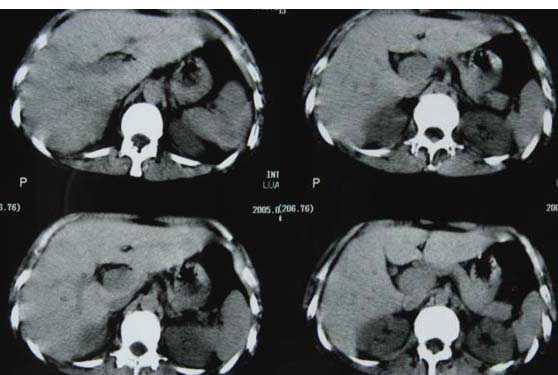

肝癌、肺转移。

1双肺支气管扩张  2双肺多发块状影,考虑:转移瘤;3肝门区圆形软组织影,先考虑:转移淋巴结可能性大.

肝癌、肺转移 支持

4、建议肝脏增强检查。

3、建议肝脏增强检查

1双肺多发块状影,考虑:转移;2双肺支气管扩张;3建议肝脏增强检查。

考虑:1、肺转移;

1肺转移瘤 2肝门区圆形软组织影,考虑淋巴结转移

1、肺转移;

3、建议肝脏增强检查。